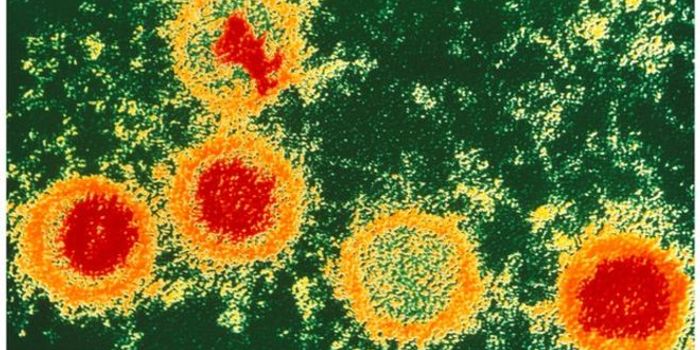

FEB 16, 2017MicrobiologySpoiler alert, you’re infected with Epstein-Barr virus. Well, you’re probably infected - nearly 98% of peopl ...

APR 16, 2018ImmunologyThe repercussions of an infection with Epstein-Barr virus (EBV) may not end with mononucleosis, “mono” or &l ...